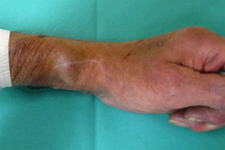

Behandlung des Dialysezuganges:

Patienten die sich einer regelmäßigen Blutwäsche unterziehen müssen (Dialyse), haben dafür einen operativ geschaffenen Gefäßzugang zum Punktieren (Dialysefistel/Dialyseshunt). Dazu wird eine Hautvene direkt an eine Arterie angeschlossen. In dieser Shuntvene können Einengungen und Verschlüsse auftreten, die mit vielen interventionellen Methoden behandelbar sind. Diese Behandlungen führen wir über einen Zugang in der Shuntvene meist ambulant in Zusammenarbeit mit der jeweiligen Dialyseeinrichtung durch.